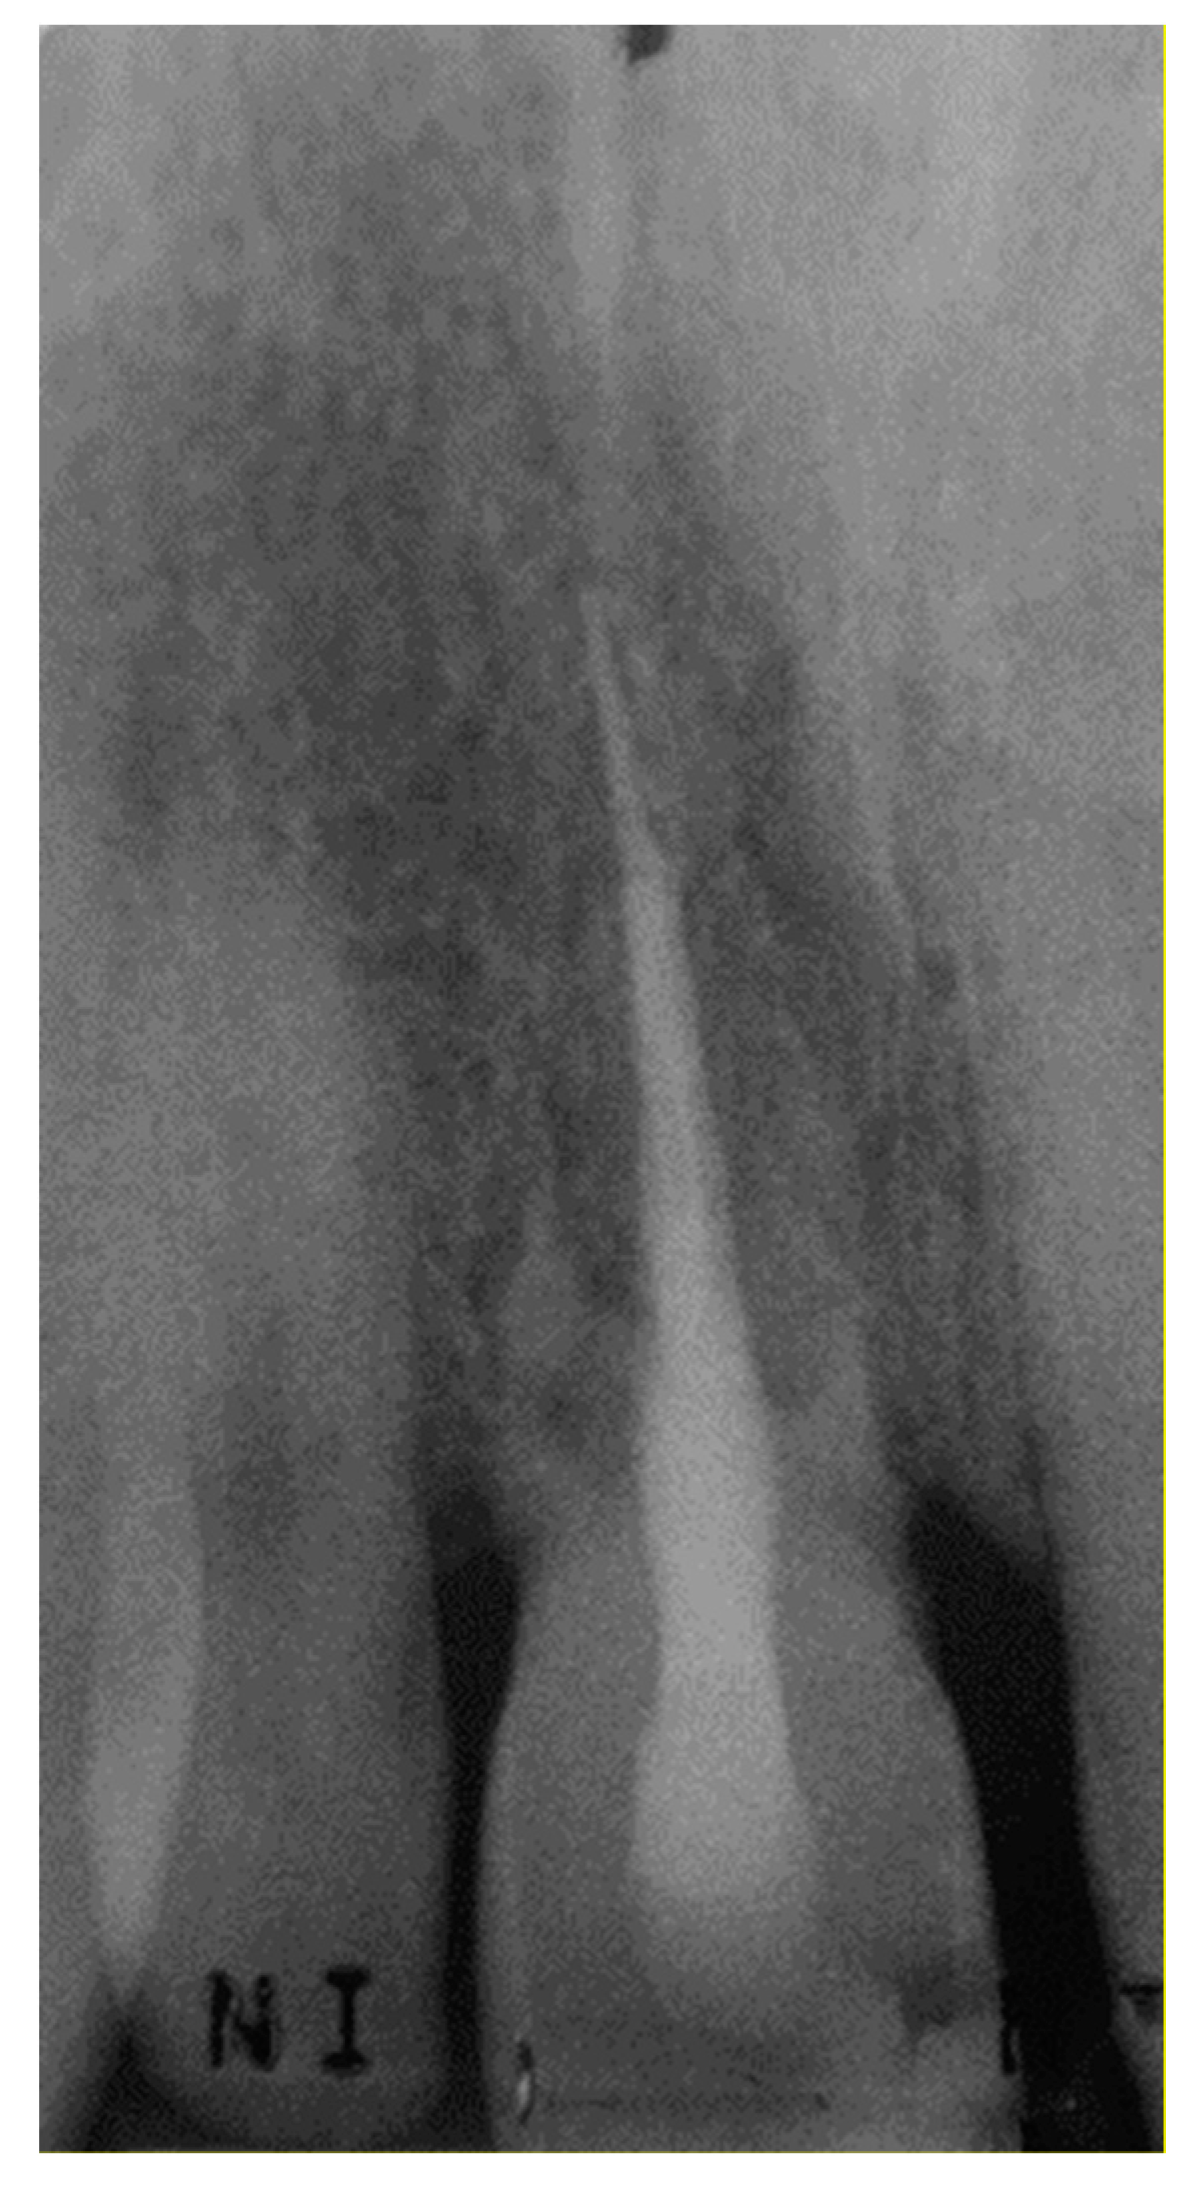

Survival of a Maxillary Incisor in an Adolescent Male 16 Years after Its Delayed Replantation

2. Case Presentation